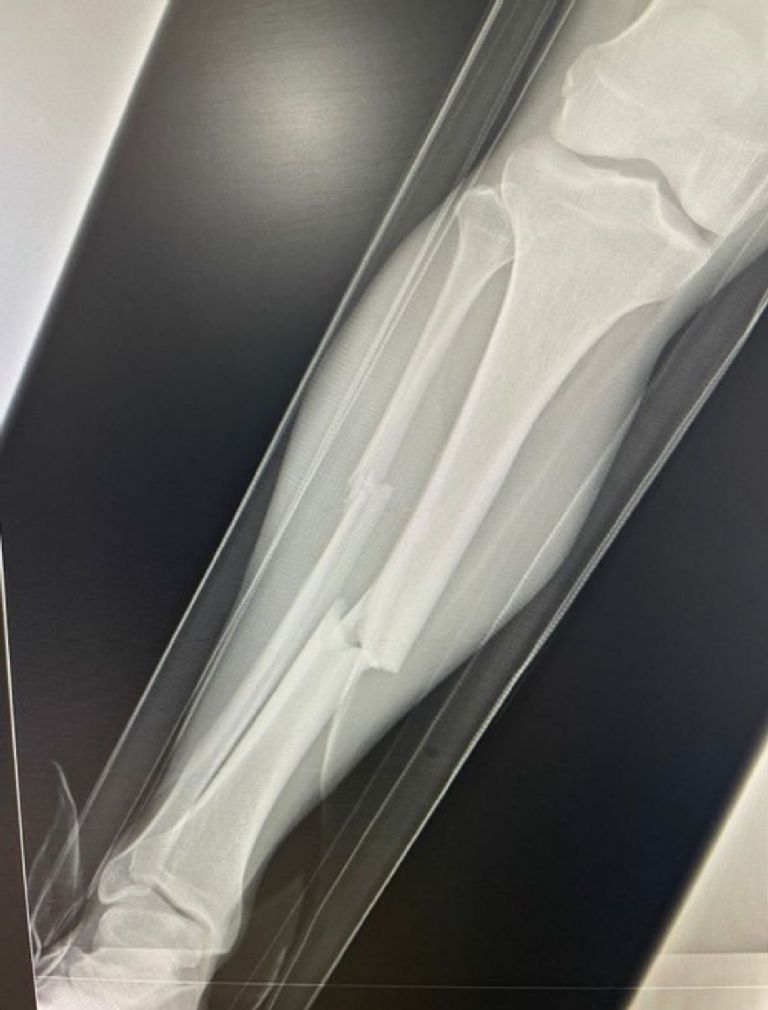

Las imágenes de la terrible fractura que sufrió el Hobbit Bermúdez tras la barrida del jugador de Dorados de Sinaloa, Luis Ruiz se han hecho virales y de hecho, fue el mismo Atlante quien confirmó que su elemento fue trasladado a un hospital tras la agresión y se confirmó que se rompió tibia y peroné de la pierna derecha, por lo que tuvo que ser intervenido quirúrgicamente.

Esta jugada quedó grabada en un video, pero también la cuenta oficial de los Potros de Hierro subió una imagen donde se aprecia cómo es que el jugador del club sinaloense le rompió la pierna, y tras esta agresión casi se armó la campal en el Estadio Ciudad de los Deportes, en el minuto 42 del primer tiempo.